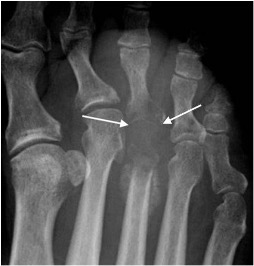

Sero-negative spondyloarthropathy

- Includes ankylosing spondylitis, psoriasis and Reiter’s syndrome; linked to HLA B27 antigen complexes

- Usually involves interphalangeal joints in an asymmetrical distribution

- Soft tissue swelling leads to dactylitis or ‘sausage digits’

- Loss of joint space and ill-defined erosions with proliferative new bone formation and periostitis

- Erosion of bone end into a sharpened pencil shape giving a ‘pencil in cup’ deformity

- Severe forms progress to ankylosis

- Fluffy new bone formation and erosions may occur at the calcaneal insertions of the Achilles and plantar fascia

Psoriatic arthropathy with new bone proliferation (arrowhead) and ‘pencil in cup’ appearance (arrow)